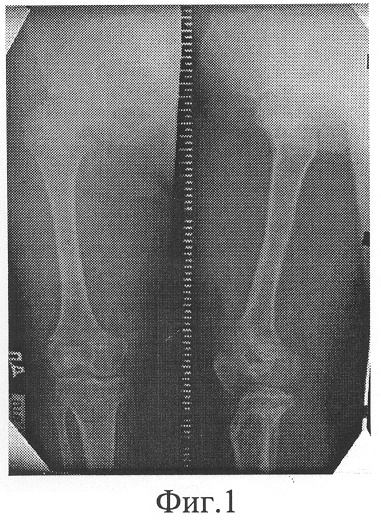

Больная М.,13 лет, поступила в клинику с диагнозом: Ахондроплазия, низкий рост (фиг.1). Для увеличения размеров конечностей больной выполнена операция: двойные остеотомии бедер, остеосинтез аппаратом внешней фиксации.

В ходе операции после анестезии и обработки операционного поля провели фиксирующие спицы через зоны проксимального и дистального метаэпифизов бедренной кости, а также через ее диафизарную часть в средней трети. Свободные концы спиц закрепили на внешних опорах аппарата, которые соединили между собой с возможностью дозированного перемещения и углового разворота.

Вслед за этим через разрезы мягких тканей произвели поперечную остеотомию в проксимальном и дистальном отделах бедренной кости. Аналогичным образом произведено нарушение целостности и остеосинтез другого бедра. Операцию завершили выполнением контрольной рентгенографии, ушиванием ран и наложением асептических повязок.

В послеоперационном периоде, начиная с 5-7 дня, производили дозированное продольное перемещение выделенных фрагментов обеих бедер. После появления рентгенологических признаков формирования костного регенерата в зонах дистракции – на 10 день – промежуточные фрагменты дозированно, в течение 5-ти дней, угловым разворотом средних опор отклонили от продольной оси сегментов на 15 градусов (фиг.2). При этом положение проксимального и дистального фрагментов оставили неизменным. Сохраняя приданное положение промежуточных фрагментов, продолжали продольную дистракцию до восстановления длины сегментов. Темп перемещения варьировали в пределах 0,5-1,0 мм в сутки на каждом из уровней дистракции, общая продолжительность которой составила 57 дней. Срок последующей фиксации в аппарате – 39 дней (фиг.3, 4). После демонтажа аппарата дополнительной иммобилизации конечности не производилось; больная прошла курс ЛФК.